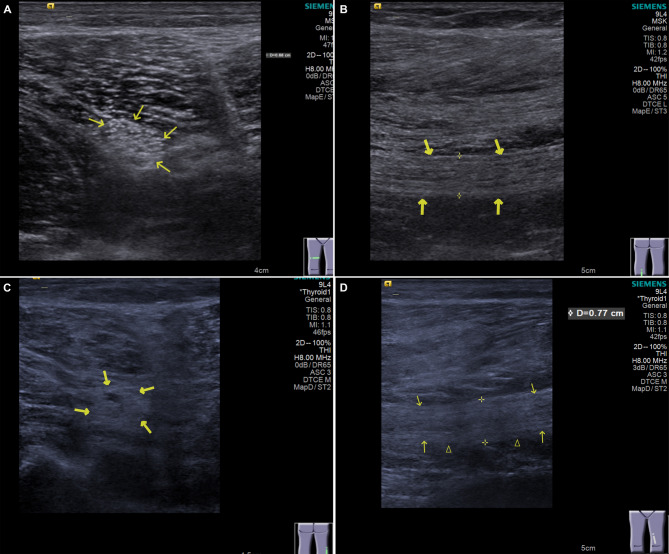

Method: 182 patients with T2DM, 137 patients with diabetic polyneuropathy, and 198 healthy volunteers were included in this retrospective cross-sectional diagnostic study. Sciatic neuropathy was evaluated through Doppler ultrasound examination with a VTIQ quantitative analysis system to acquire elastic modulus, cross-sectional area (CSA) and shear wave velocity (SWV). Nerve conduction velocity (NCV) was also evaluated via neurophysiological examination. Logistic regression was used to analyze odds ratios (OR) related diabetic polyneuropathy. The diagnostic accuracy of the VTIQ technique-acquired index on diabetic polyneuropathy was analyzed using the receiver operating characteristic (ROC) curve.

Results: VTIQ technique-acquired indexes all differed significantly among three study groups, among which Elastic modulus and CSA were independently related to diabetic polyneuropathy risk according to the logistic regression analysis. NCV was also an independent risk factor for diabetic polyneuropathy. ROC analysis revealed that Elastic modulus, CSA and NCV can distinguish diabetic polyneuropathy patients from T2DM cases with the AUC of 0.797, 0.654 and 0.775 respectively. But their combination achieved the highest diagnostic value (AUC = 0.883). CSA and SWV of the sciatic nerve are positively correlated with visual analog scale (VAS) scores.